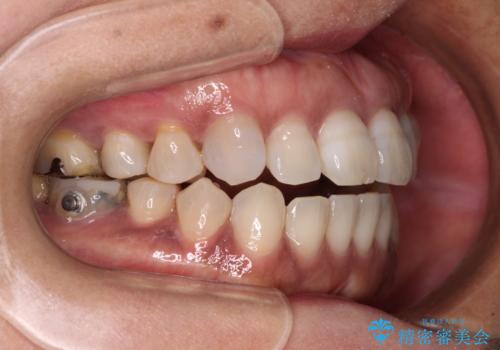

開咬の治療は、前歯を閉じるように動かすとともに、上下臼歯を圧下(骨内にめり込ませる)させることで進めて行きます。

インビザラインは臼歯の圧下を効果的に行えるため、インビザラインを用いて矯正治療を行うこととしました。

また、下顎大臼歯に根管治療が必要な歯があるため、矯正治療と並行して治療を行い、矯正後に補綴治療することとしました。